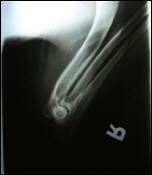

Allys Ellbogen gestreckt

ED: 0/0